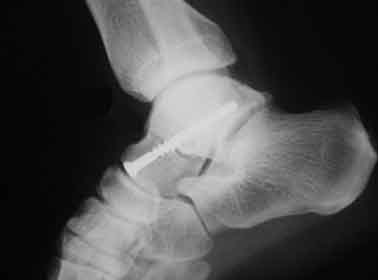

5. 거골 골절

교통사고등에서 주로 보이는 골절입니다. 이 골절의 특징으로서 혈류장애에 의해 뼈의 괴사를 일으킬 수 있다고 알려져 있어 주의가 필요합니다. 골절부의 어긋남이 없다면 깁스 등의 보존적 치료로 가능하고, 어긋남이 있다면 스크루 등을 이용하여 수술을 할 가능성이 있습니다.